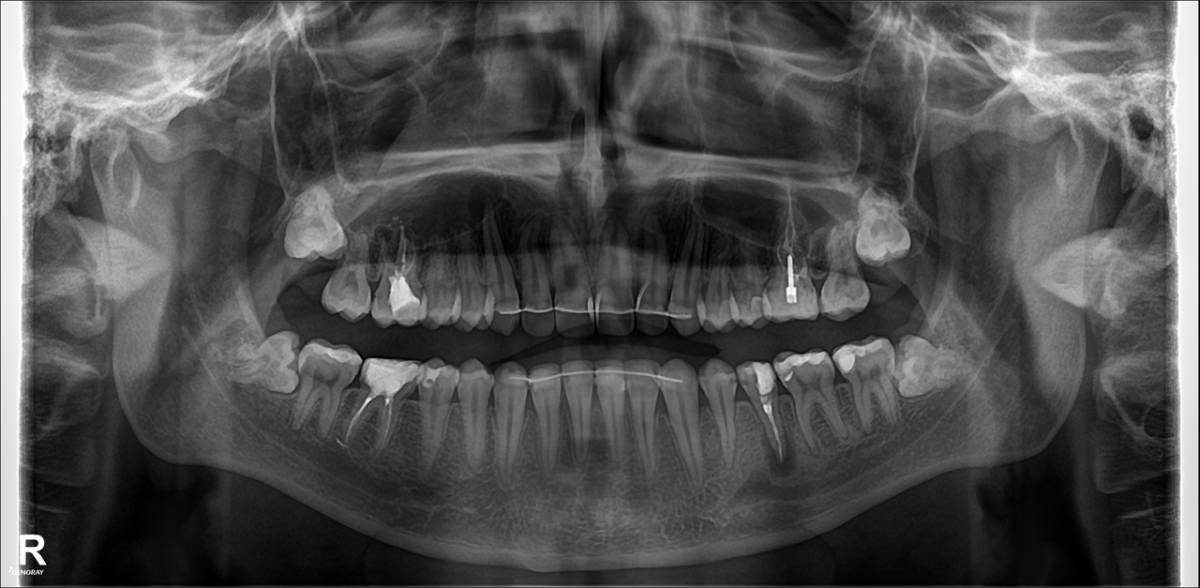

Dimedr Опубликовано 1 час назад Поделиться Опубликовано 1 час назад Добрый день. Вечером заболела верхняя десна, боль отдавала в клык. Опухла щека, утром поехал в клинику, сказали верхний зуб 16, нужно удалять, т.к. там образовался гной , который со слов врача уже проедает кость. И сказали нижний зуб 35, тоже нужно удалить, а то скоро так же заболит, т.к. на корне киста. В итоге удалили оба зуба, в 35 вкрутили штифт. При удалении сказали гноя не было на 16, но кисту на 35 нашли. Решил попросить снимки челюсти, с начала отказывались давать, из-за чего закрались подозрения. На повторном осмотре хирург сказал, все отлично. Но вечером дома обнаружил, что над клыком рядом с 16 зубом, десна вспухла и побелела. Скажите все ли верно сделали ? Для уточнения, год назад снял брекеты. Ссылка на комментарий